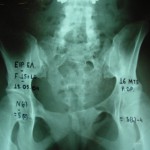

Εικόνα 1

Προεγχειρητική μετωπιαία ακτινογραφία της σπονδυλικής στήλης και της πυέλου. Παρατηρείται η ύπαρξη κατάγματος του ιερού οστού στη μεσότητα του.